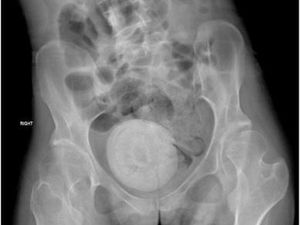

Seorang wanita 30 tahun terkejut saat dokter menemukan dua batu besar di vaginanya saat konsultasi fertilitas. Satu-satunya kasus yang dilaporkan di Indonesia.